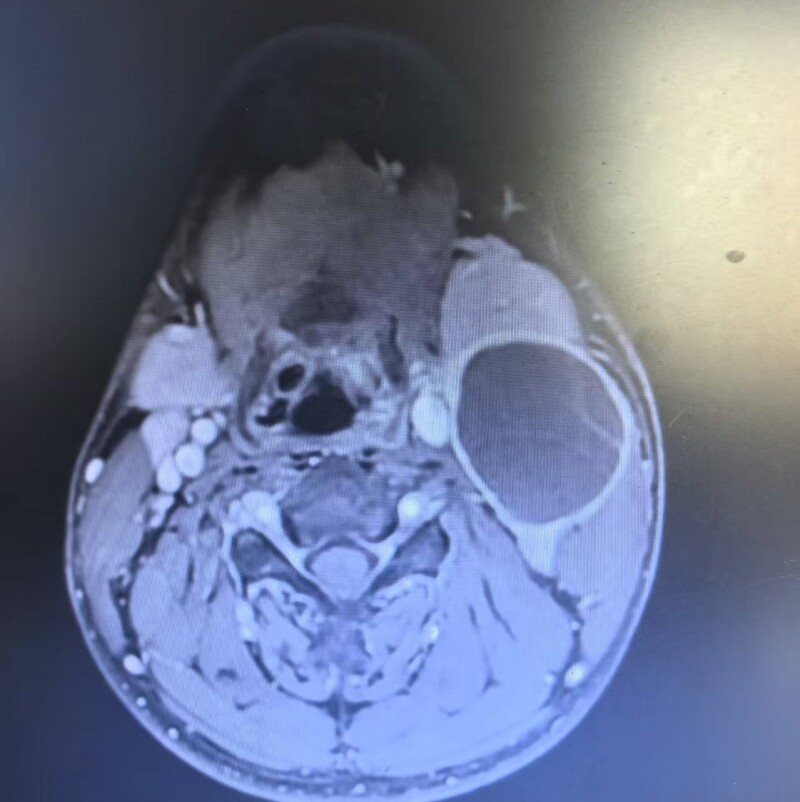

患者曹某,17岁,因发现颈部左侧无痛性肿块10余天,且近期感觉吞咽不适与声音嘶哑前来就诊。经检查,发现其左侧颈动脉有一大小约5.5×3.8cm的囊性占位性病变。影像学显示,肿瘤位置极深,与颈内动脉、颈外动脉关系密切,与迷走神经、舌下神经等重要结构粘连严重,手术难度和风险极大。

面对挑战,耳鼻咽喉头颈外科团队进行了周密的术前准备。利用三维重建技术精准还原了肿瘤与周边血管、神经的立体关系,并制定了详尽的手术预案及应急措施。

县人民医院耳鼻咽喉头颈外科主任李贤权:“颈动脉三角区解剖结构复杂,是颈动脉、多项颅神经、颈深淋巴结等关键结构的‘交通要道’。此区域的肿瘤手术,犹如在‘悬崖边上跳舞’,要求术者不仅要有精湛的技艺,更要有极大的耐心和丰富的解剖知识。本次手术的成功,得益于术前精准的影像评估、术中精细的显微操作和麻醉团队的通力协作,是多学科协作(MDT)模式的又一成功典范。”